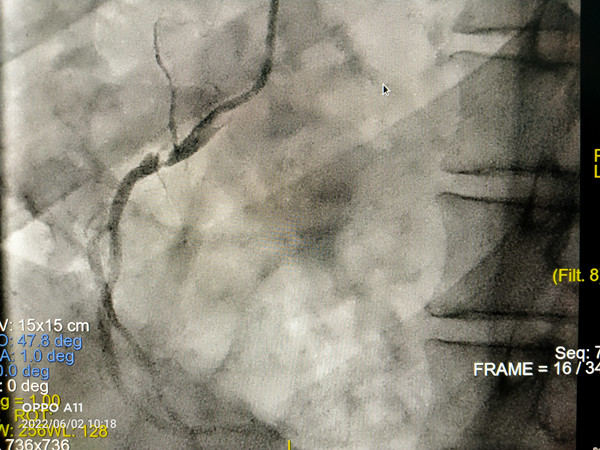

图1

在我院心外科裴斐主任医师,麻醉科刘鹏斌主任医师、罗斌主治医师,超声科韩东刚副主任医师、金鑫主治医师,曹春晖护士长领导的护理团队等多学科协助下,韩振华主任、王新宏副主任医师、刘小军主治医师等先为患者行冠脉造影提示右冠近段95%狭窄(图1),先行PCI干预,右冠植入3.0x22mm支架1枚(图2)。后成功为患者植入TAV24mm VitaFlow瓣膜系统,DSA造影显示主动脉瓣位置良好,未见明显瓣周漏(图3),左右冠脉造影正常,术后即刻心脏超声示最大跨瓣流速129cm/s,最大跨瓣压差7mmHg(图4),顺利结束手术。